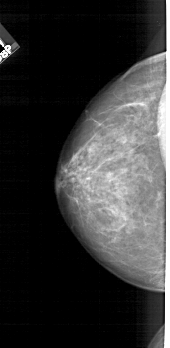

A_1715_1.RIGHT_CC

RIGHT_CC LINES 4591 PIXELS_PER_LINE 2251 BITS_PER_PIXEL 12 RESOLUTION 43.5 OVERLAY